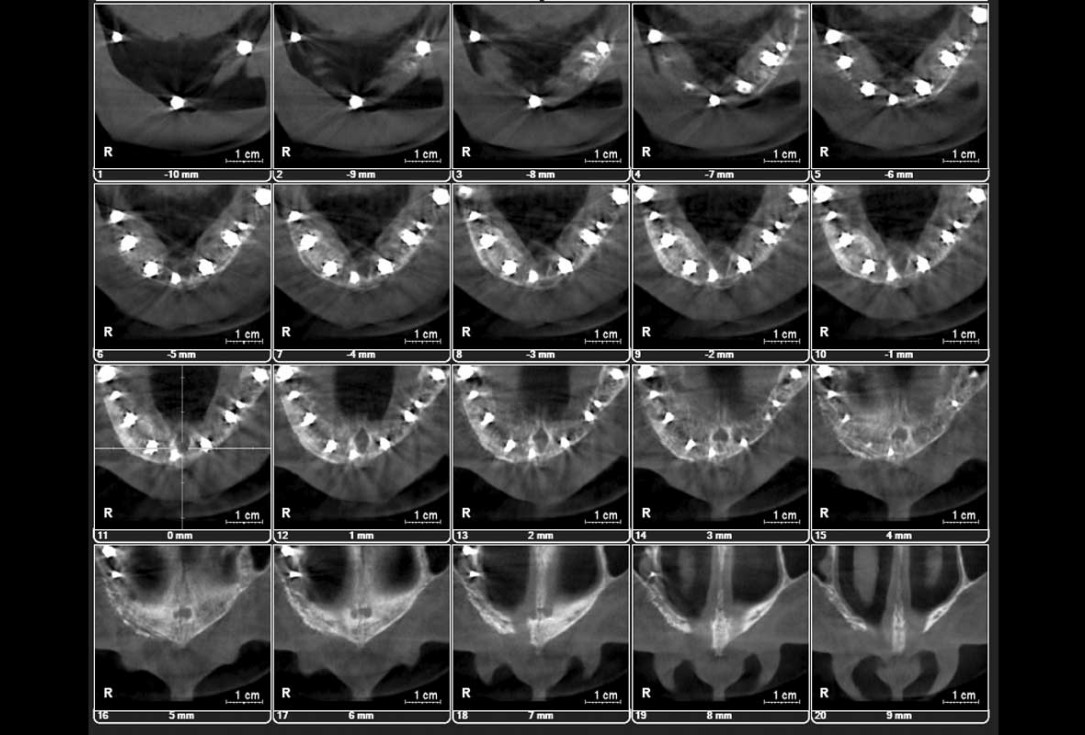

Initial x-ray showing bone loss around implants placed 5 years ago in another dental clinic